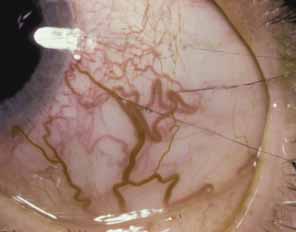

The second form of isolated trabeculodysgenesis has a concave iris insertion. The plane of the iris is posterior to the scleral spur. However, the anterior stroma continues over the trabecular meshwork, obscuring the scleral spur and ending just posterior to Schwalbe's line (Fig. 2).

Fig. 2 Concave iris insertion in trabeculodysgenesis. Superficial iris tissue wraps around the angle recess and covers the internal surface of the trabeculum. This may take the form of dense sheets (left) or an arborizing network (right). This is different from the small processes seen in the anterior iris insertion. (Hoskins HD Jr, Shaffer RN, Hetherington J: Anatomical classification of the development of glaucomas. Arch Ophthalmol 102:1331, 1984. Copyright © 1984, American Medical Association.)